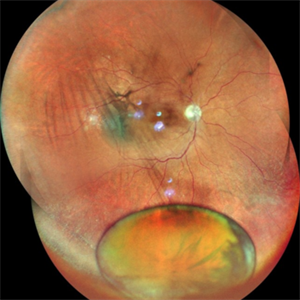

Old Supero-Temporal Branch Retinal Vein Occlusion with Macular Hole

Fundus photograph of a 36-year-old female with supero-temporal branch retinal vein occlusion with macular hole in right eye.

Photographer: Dr. Akansha Sharma- Retina Foundation, Ahmedabad

Condition/keywords: branch retinal vein occlusion (BRVO), macular hole